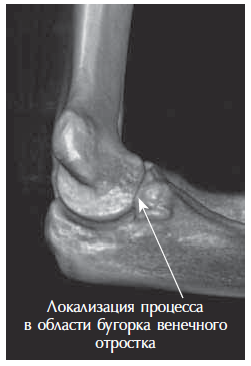

Radiography and computed tomography were performed (Figures 1–3). An aseptic necrosis was detected in the region of the tubercle of the coronary process in the fragmentation stage.

Fig. 1. Radiograph of the left elbow joint. Fragmentation stage of the region of the coronoid process tubercle

Fig. 3. Computed tomography in 3D mode